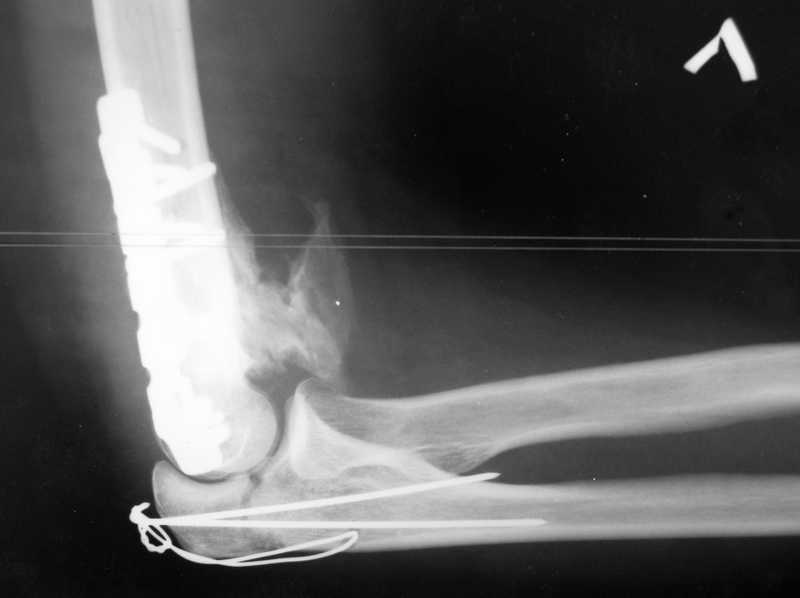

У пациентки 42 лет после операции остеосинтеза чрезмыщелкового перелома плеча, выполненной в нашей клинике 2 месяца назад, на контрольных R-граммах имеется гетеротопический оссификат по передней поверхности плеча.

Оперирована по методике АО, после операции максимально рано начала заниматся ЛФК. В настоящее время основная жалоба пациентки на ограничение сгибания в локтевом суставе. Клинически объем движений: сгибание 90 градусов, разгибание 170 градусов, ротационные движения в полном объеме. Привожу снимки сразу после операции и через 2 месяца. (На рентгенограммах после операции в мягких тканях по передней поверхности плеча имеется небольшой костный фрагмент, но его ширина во фронтальной плоскости не более 1 мм., обнаружен был по снимкам после операции. Интраоперационно основные крупные фрагменты отрепонировались хорошо, объем движений был сгибание до 75 градусов, разгибание 175 град.)

Пациентка неудовлетворена объемом сгибания, хотя была предупреждена о высокой вероятности ограничения движений. Профилактика гетеротопической оссификации (прием индометацина) не проводилась, т.к. имелась язвенная болезнь, да и эффект от его приема считаю сомнительным.